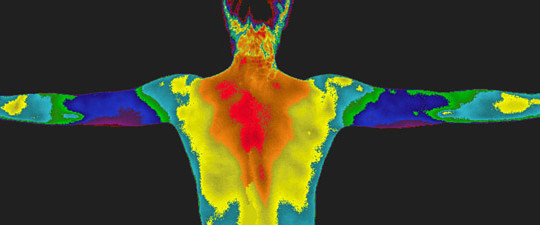

Ефективність передопераційної діагностики з використанням КТ-ангіографії при реконструктивних втручаннях на нижніх кінцівках

Авторы: С. В. Слєсаренко, П. О. Бадюл, С. О. Мунтян, К. С. Слєсаренко, О. О. Ковбаса Статья опубликована в журнале: Клін. хірургія. – 2016. – № …